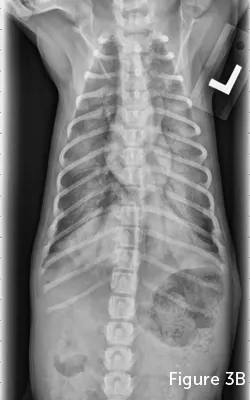

A person is gently holding a black and white cat's mouth open to examine its oral cavity, revealing a pink tongue and a small lesion on the underside of the tongue. The setting appears to be a veterinary clinic, with the focus on the cat's dental health.

FIGURE 1

Electrical burn of the lateral aspect of a cat’s tongue caused by the cat chewing on an electrical cord.

Clinical Signs

NCPE patients typically exhibit signs of respiratory distress, including tachypnea, dyspnea, and potential pulmonary crackles. Variability of underlying causes (eg, electrocution causing ulceration of the tongue and oral cavity [Figures 1 and 2]) necessitates a complete physical examination. Patient anxiety and respiratory distress may prohibit complete examination on presentation; if so, a partial examination can be performed before placing the patient in an oxygen cage and completing the examination.